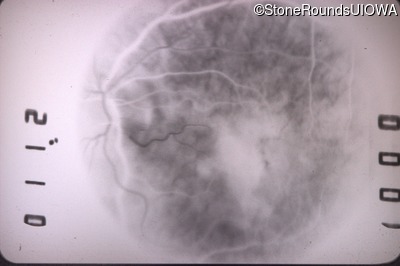

Fluorescein Angiography - Right - 20/40 -2

Exemplar

Fluorescein Angiography - Left - 20/400